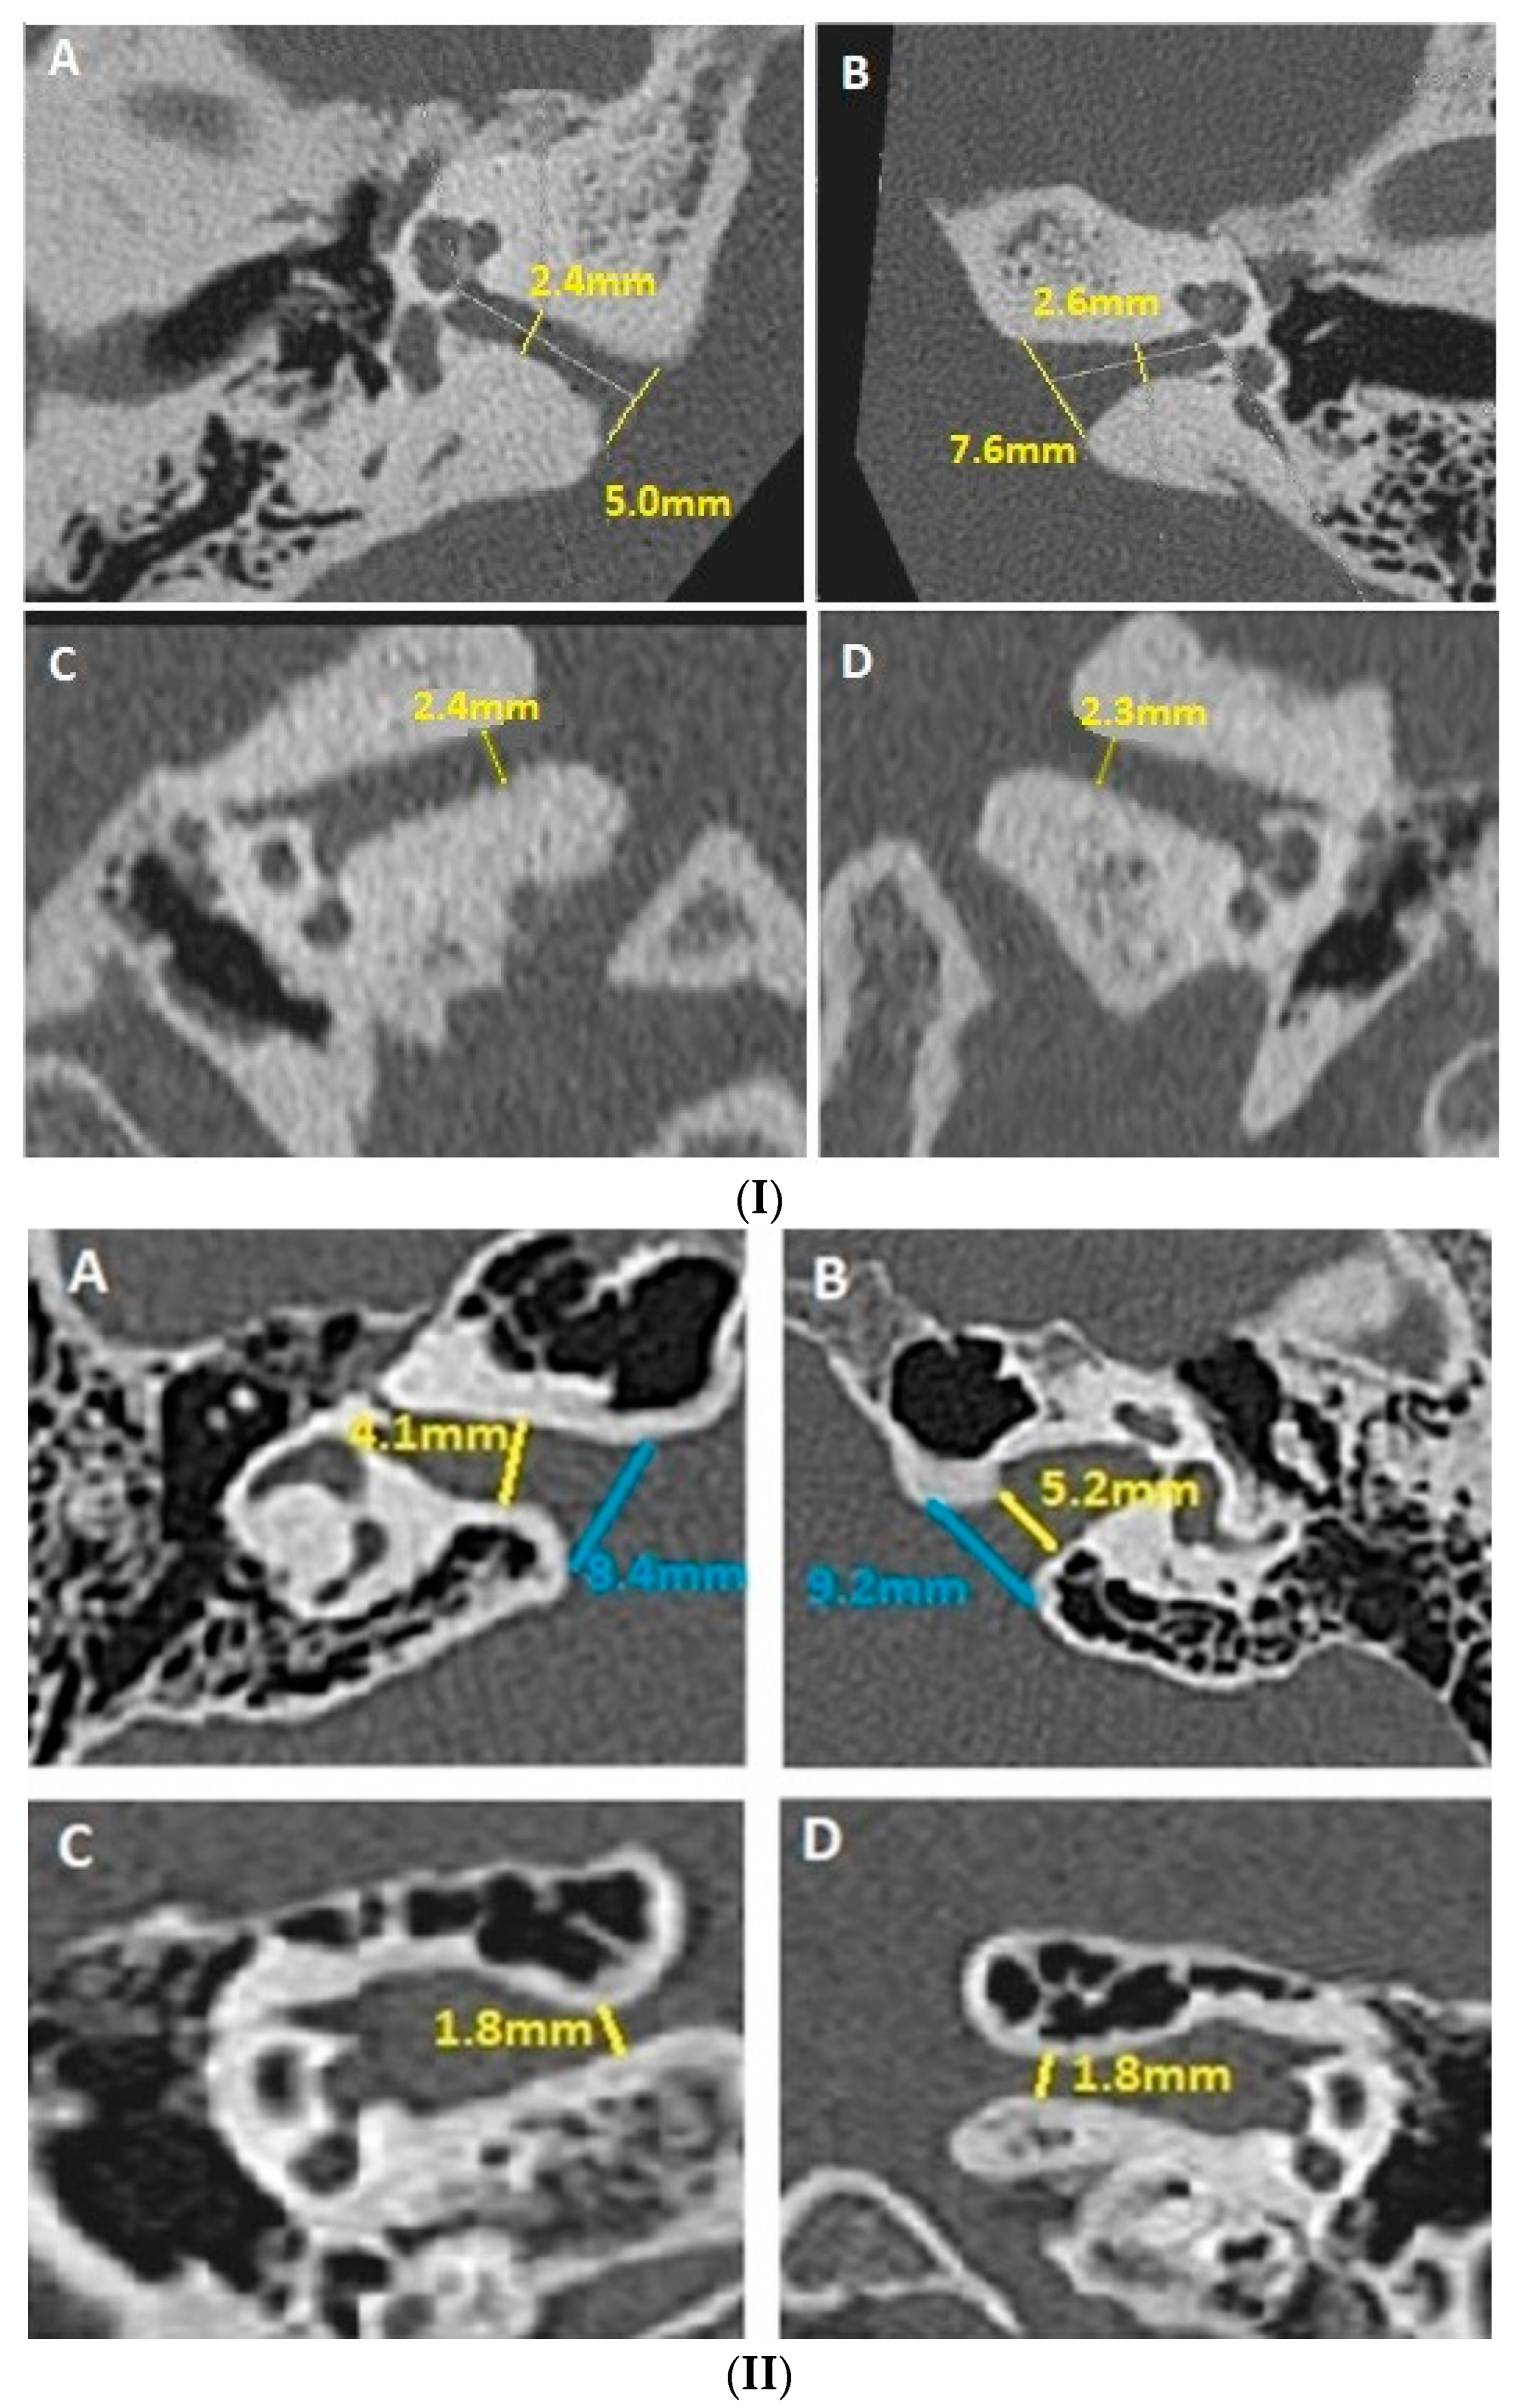

- Evaluation of the smallest anteroposterior and craniocaudal IAC diameters, both in the axial and coronal planes, after measuring the IAC length (Figure 1(I,II));

- Evaluation of anteroposterior and craniocaudal diameters of the IAC (Figure 2(I,II)).